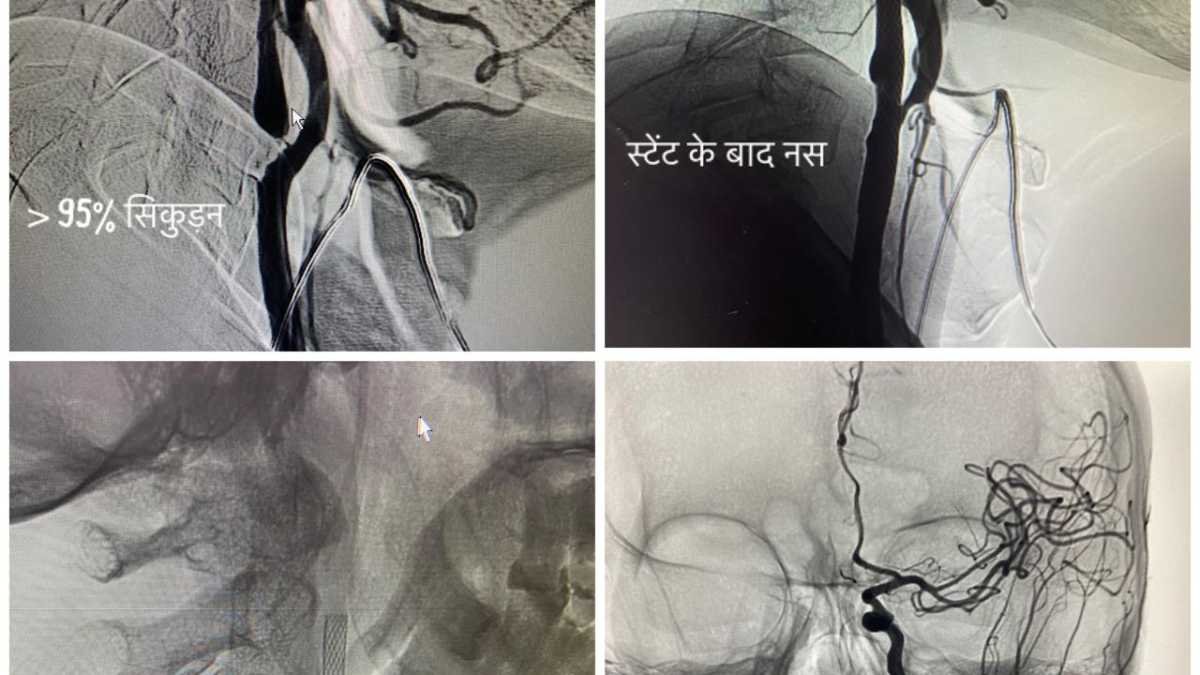

एम्स ऋषिकेश में अब उच्च तकनीकी वाले एंडोवेस्कुलर न्यूरोइंटरवेंशन शुरू

एम्स,ऋषिकेश की कार्यकारी निदेशक एवं सीईओ प्रोफेसर (डॉ.) मीनू सिंह के निर्देशन में संस्थान के इंटरवेंशन रेडियोलॉजी विभाग में उच्च…